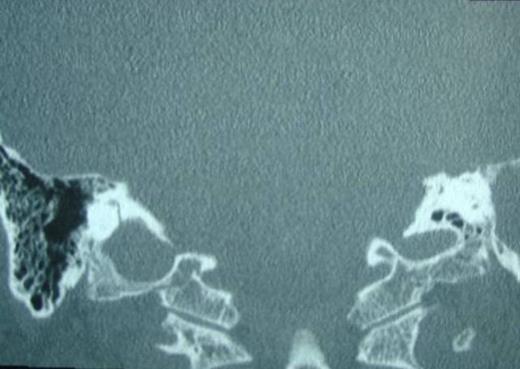

A 52 –year-old male with bilateral deafness and right facial nerve palsy presented to our clinic. The patient who was referred for consideration of cochlear implantation had a history of head injury 8 months before. An initial CT scan 2 months following his injury showed a transverse temporal bone fracture on the right side and a longitudinal one on the left side. Both cochleas appeared to be patent (Fig. 1, 2). The left ear was chosen for implantation as the injury was less severe on that side.

Right transverse fracture (black arrow) and left longitudinal fracture (white arrow)